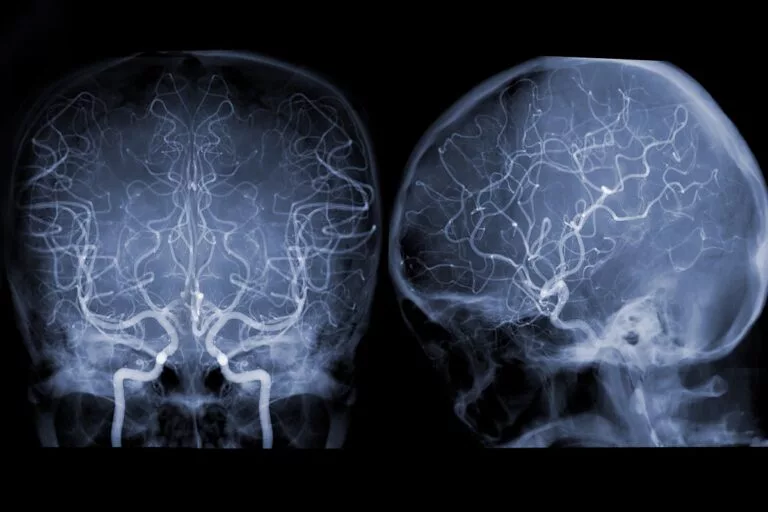

• Cognitive assessment tests (MMSE, MoCA)

• Brain imaging (CT, MRI, or PET scans)